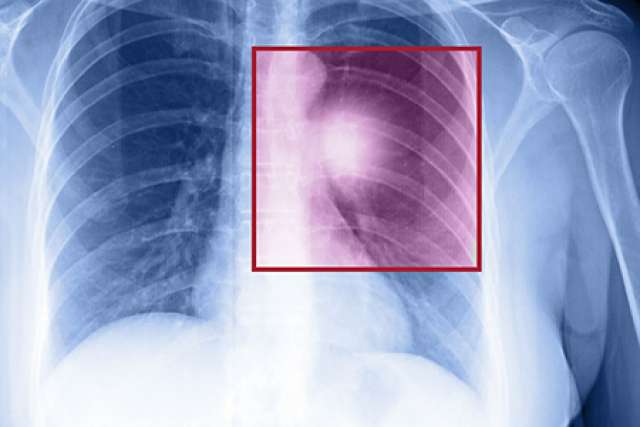

Immunotherapy improves five-year survival rate of people with advanced lung cancer

Chest scan